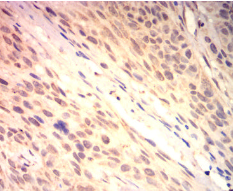

IHC    1/200-1/1000